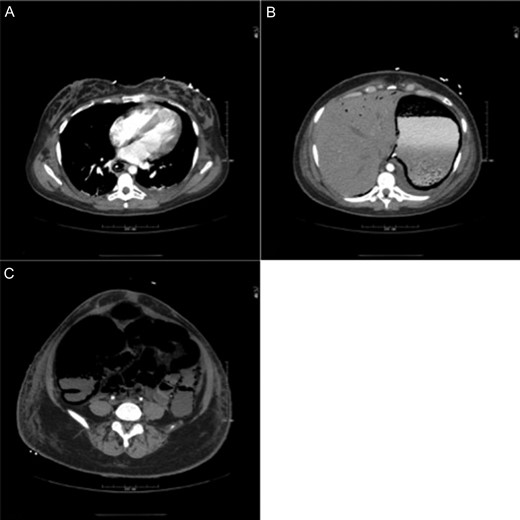

On the evening of post-burn day (PBD) 2, the patient developed a distended abdomen and became oliguric, unresponsive to volume challenge. A portable abdominal x-ray was concerning for pneumatosis of the stomach, small bowel and colon (Fig. 2). Computed tomography (CT) confirmed pneumatosis of the esophagus, stomach, small bowel and much of the colon, and hepatic portal venous gas (HPVG)—concerning for ischemic bowel (Fig. 3A–C) and prompting operative intervention. Of note, all vessels were patent. In the operating room (OR), the GI tract was distended with pneumatosis but without signs of ischemia except for a segment of mid-jejunum which was resected. She became hemodynamically unstable and thus left in discontinuity and an open abdomen.

CT showing extensive pneumatosis involving the esophagus (A), the stomach (B) and the small bowel and colon (C). Hepatic portal venous gas is notable in (B).